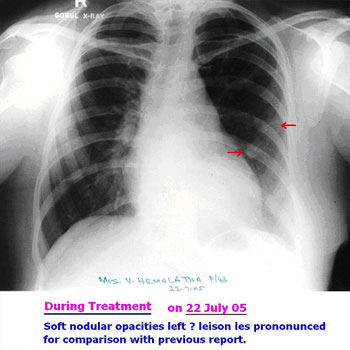

X-Ray DURING HERBAL ONCOLOGY

22-Jul-2005

SCAN AFTER HERBAL ONCOLOGY

08-Sep-2005

Ductal Cell Carcinoma

INITIAL STAGE

18-Jun-2005

Patient Name : Mrs. S R (67 / F)

Multiple non-calcific nodes seen in pre carinal and pretracheal region.Multiple well defined nodules on both lung fields consistent with secondaries.